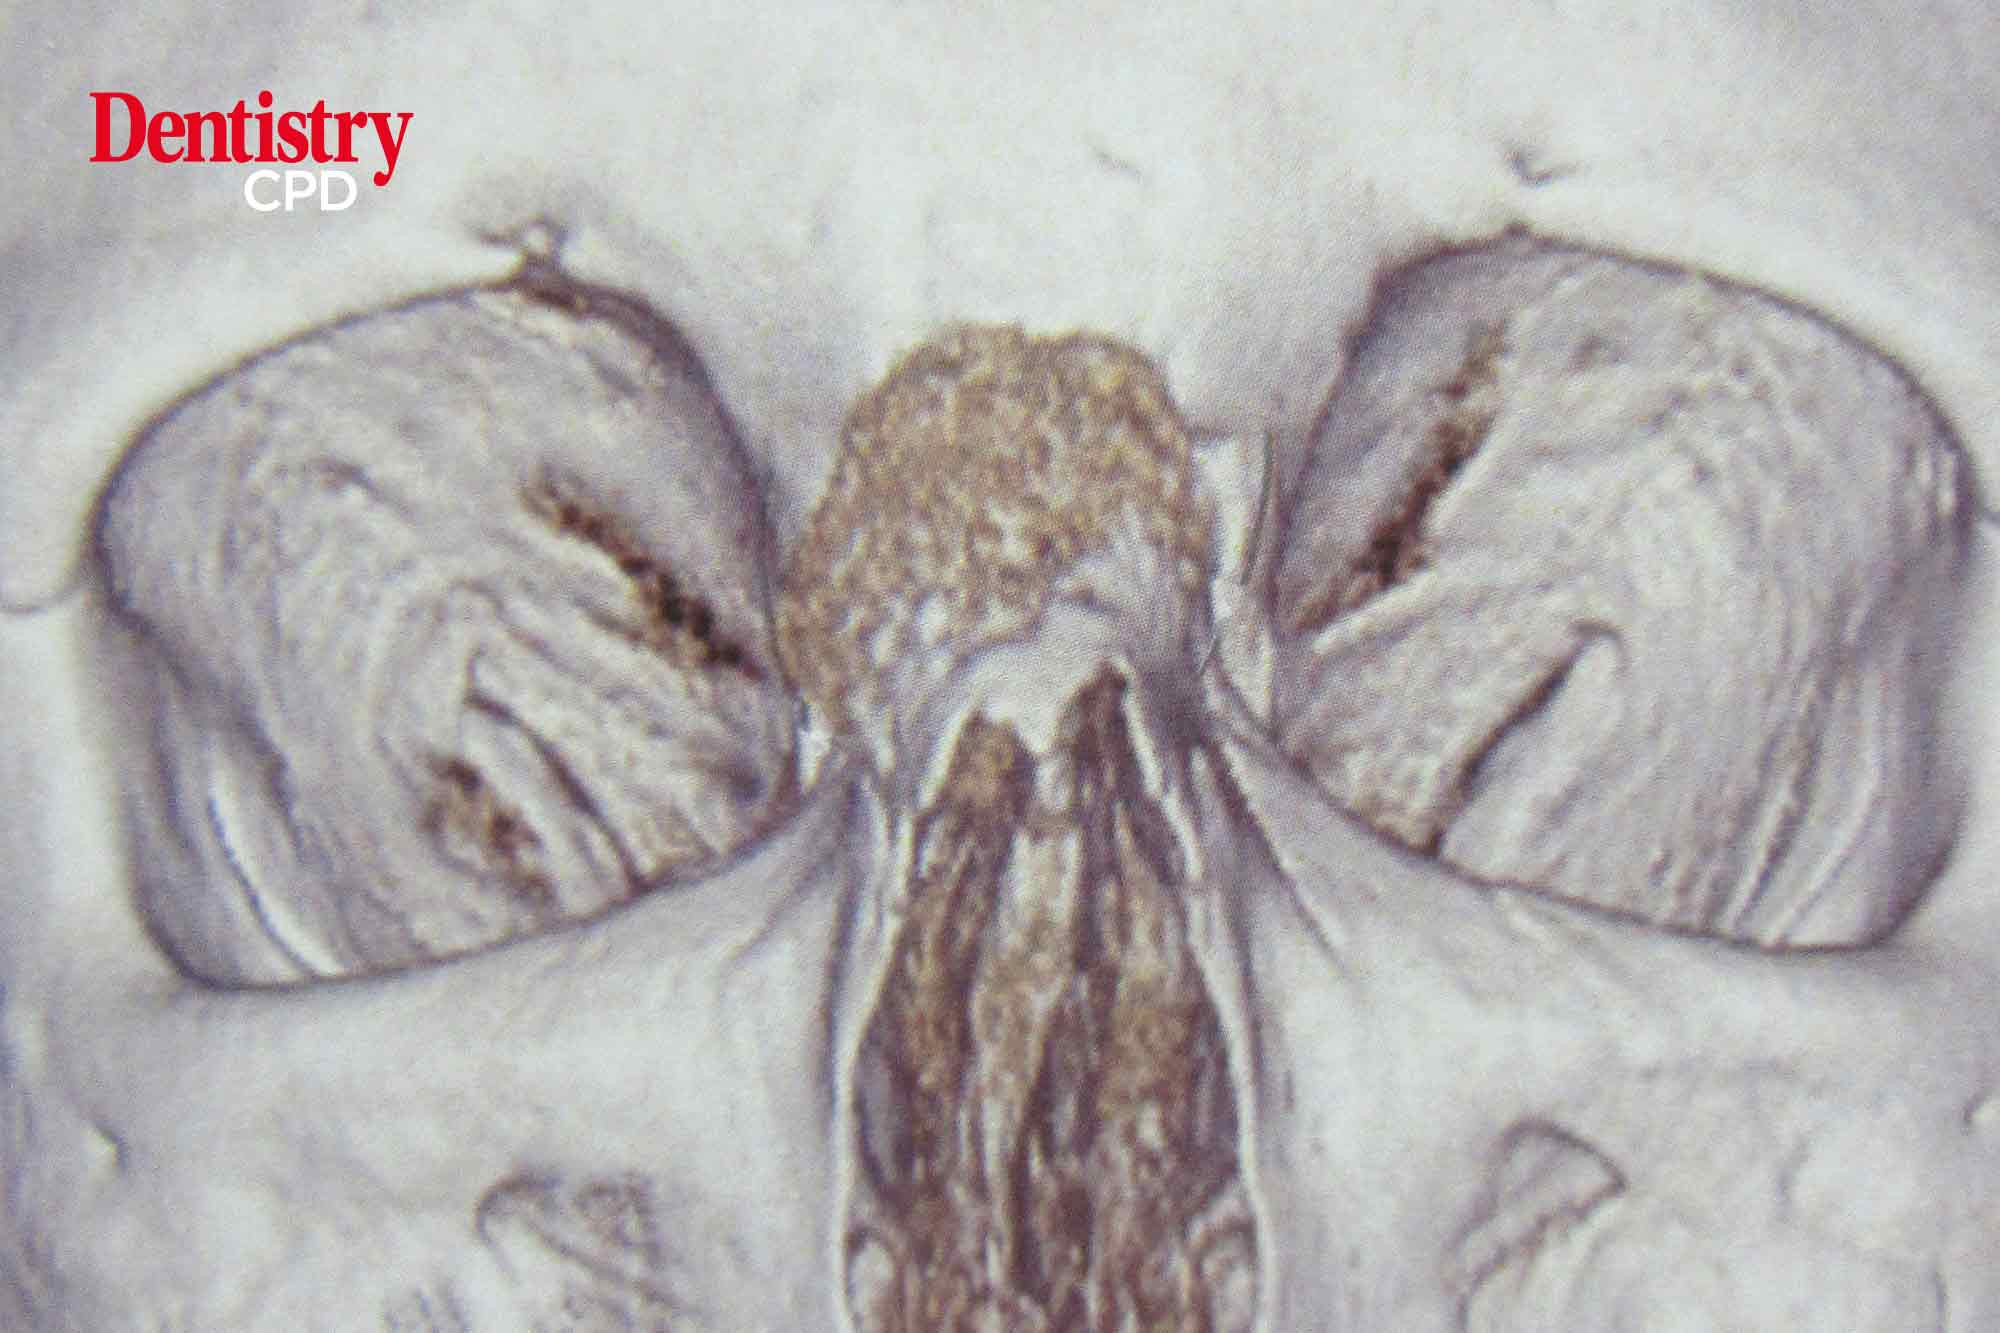

Intraosseous cavernous haemangioma of nasal bone

Nika Vafaei and Carlo Ferretti present a review of the literature and a case report of the presentation, treatment and reconstruction of an intraosseous cavernous haemangioma occurring in the nasal bridge